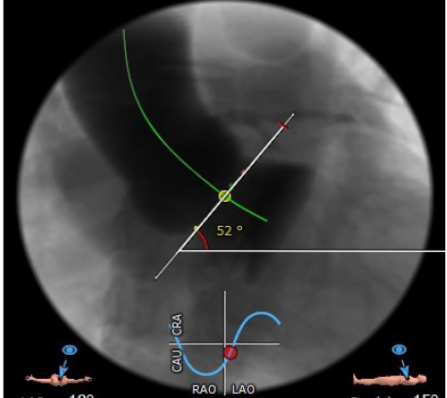

冠脉高度尚可。左冠高度:13.4,右冠高度:20.6。心脏角度52